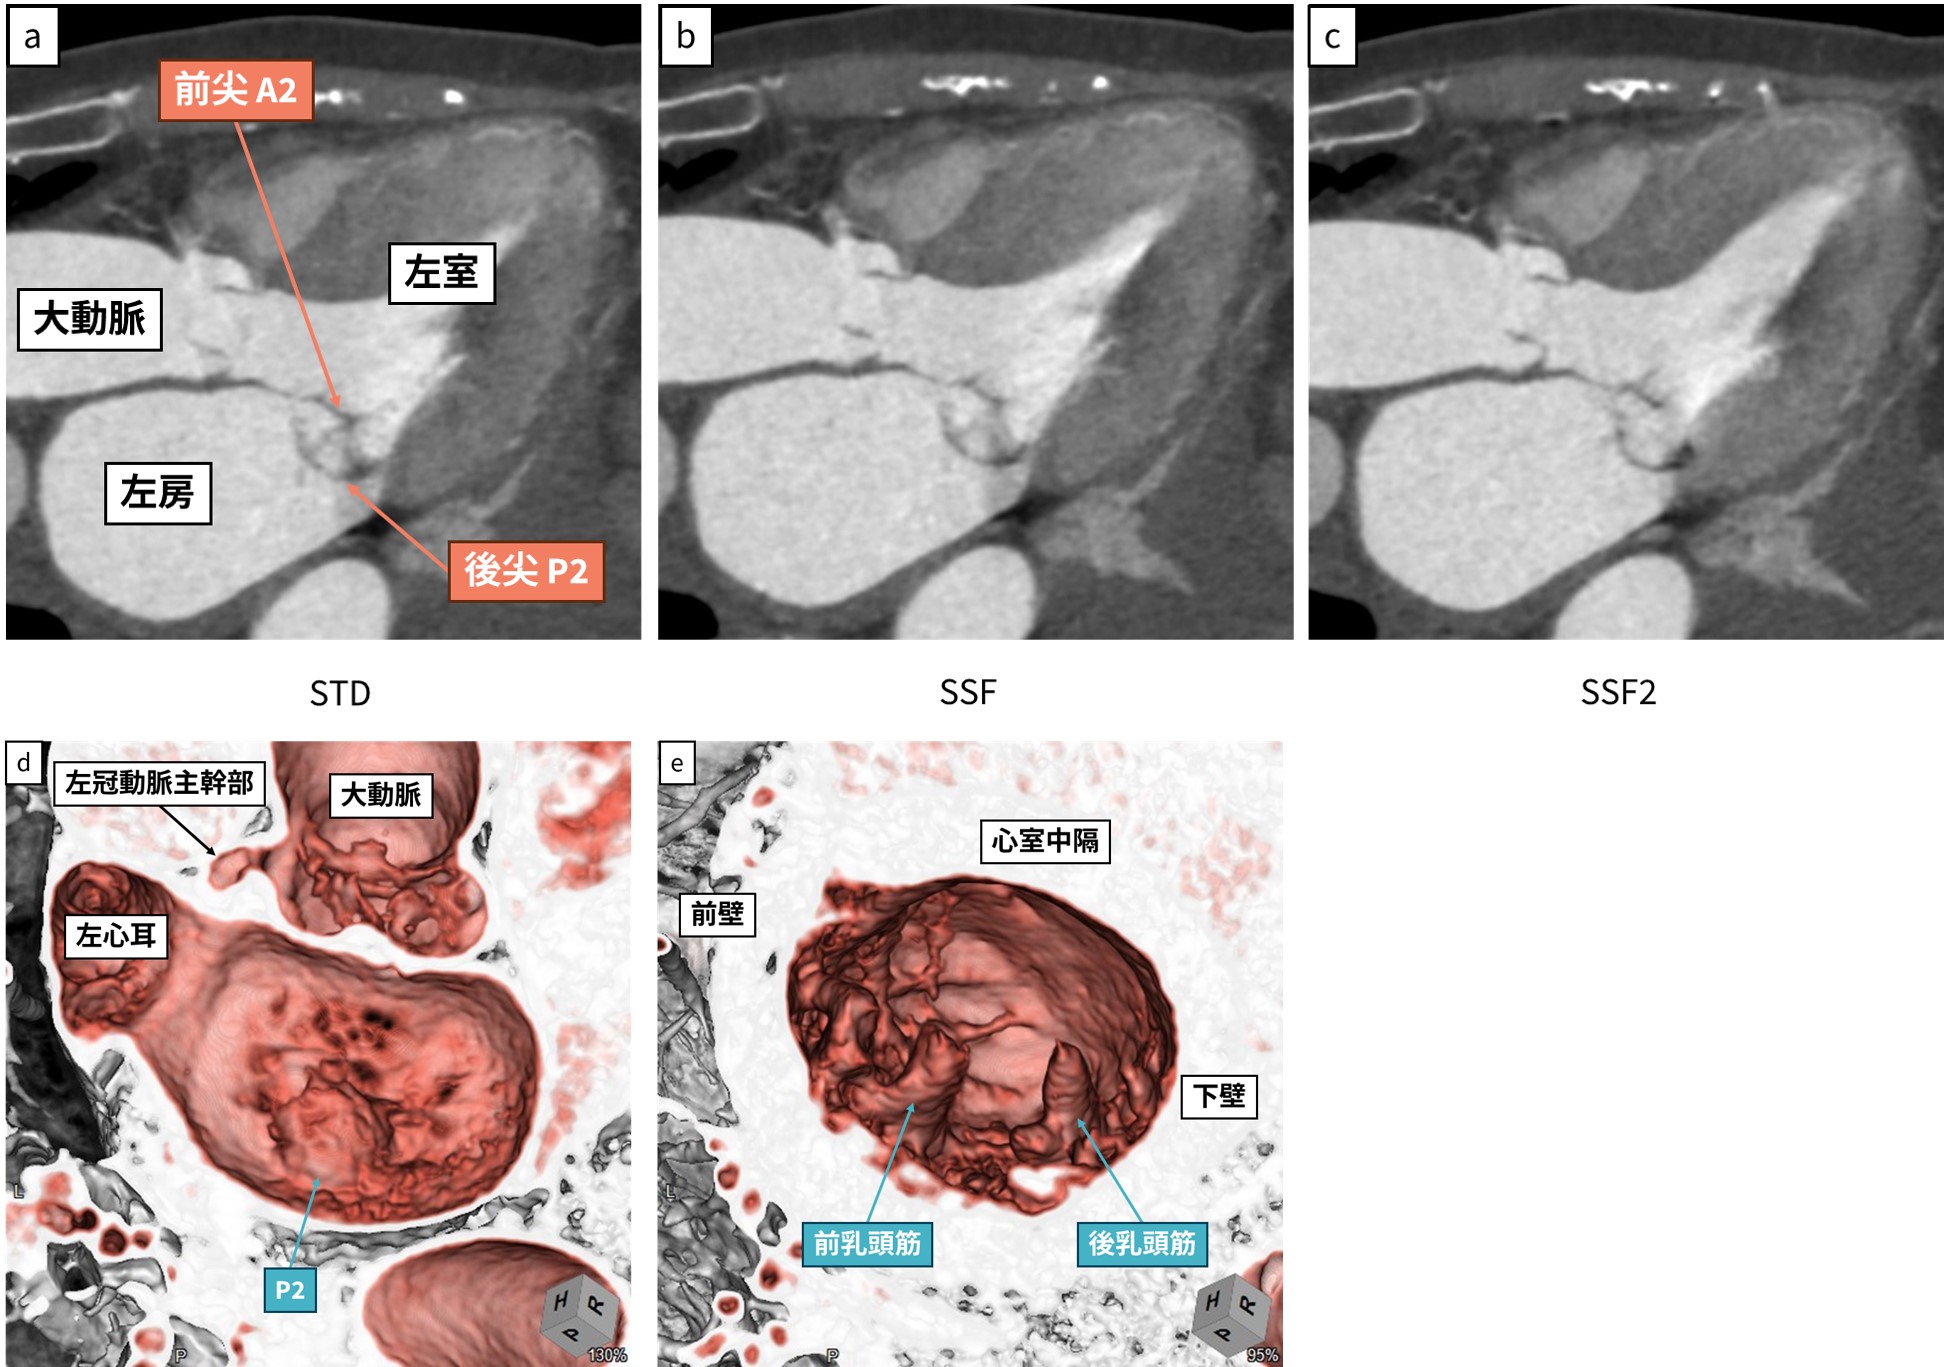

僧帽弁閉鎖不全症の診断に寄与する収縮期の前尖・後尖の各セグメントの描出能について、我々が行った5段階の視覚評価(4: 弁尖全体がブレなく描出される~0: 描出されない)では、motion correctionを施行していない画像(以下、STD)および第一世代のSSFよりもSSF2の画質スコアが有意に高かった[10] (図1,図2)。第一世代のSSFは冠動脈のブレのみを補正するのに対して、第二世代であるSSF2では冠動脈に加え心臓内の他の構造物の動きも補正の対象としており、僧帽弁の描出能が向上したものと考えられる。

図1  僧帽弁逸脱症術前症例 心拍数 110 bpm.

a-c: 心電図R-R 30 % (収縮期)におけるA2/P2三腔断像

d: 左房から僧帽弁を見たsurgeon’s view

e: 僧帽弁から左室内腔を見たsurgeon’s view

本症例では、三腔断像および3D surgeon’s viewともに後尖P2の逸脱が確認できる。

撮影時心拍は高かったが、STD(motion correctionなし)、SSFと比較して、

SSF2では後尖のアーチファクトが低減し、弁尖全体が描出されている。